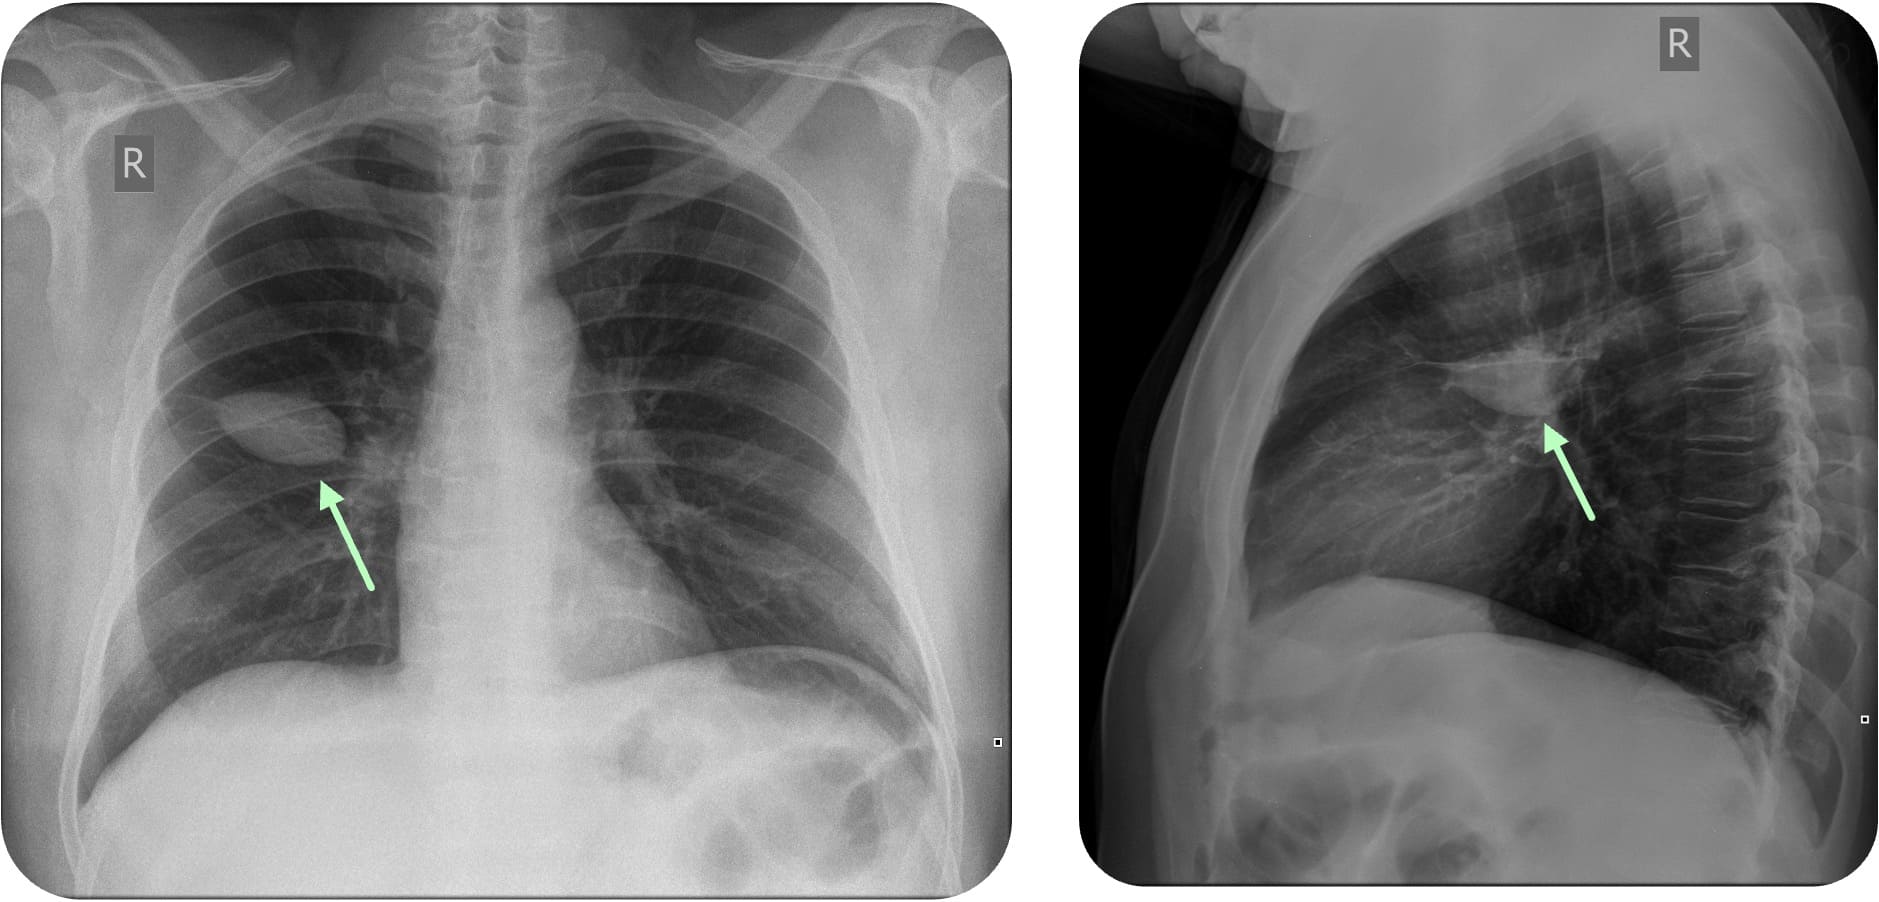

Zur Beurteilung eines Pleuraergusses wird eine Aufnahme im Stehen in 2 Ebenen angefertigt. Der Erguss sammelt sich in Richtung der Schwerkraft am tiefsten Punkt des Thorax

Da der hintere Teil des Recessus costodiaphragmaticus tiefer liegt als der vordere, lassen sich kleine Ergüsse am besten in der Seitaufnahme

Im Röntgen-Thorax

Meniskuszeichen

Der Pleuraerguss

Case courtesy of Frank Gaillard, Radiopaedia.org, rID: 25595

Case courtesy of Craig Hacking, Radiopaedia.org, rID: 80388